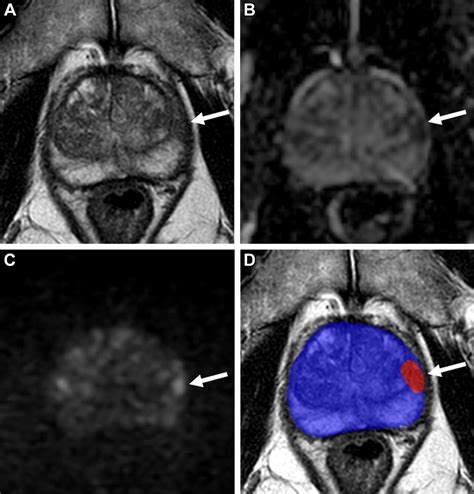

When a patient is assigned a Pi Rads 4 score, it means that there is a well-defined lesion on the MRI that exhibits characteristics highly suggestive of a potentially aggressive tumor. Specifically, for peripheral zone lesions, this means a focal, low-signal intensity lesion on T2-weighted imaging and marked diffusion restriction on Diffusion-Weighted Imaging (DWI). For transition zone lesions, it refers to a lenticular or non-circumscribed, encapsulated, moderately hypointense lesion.